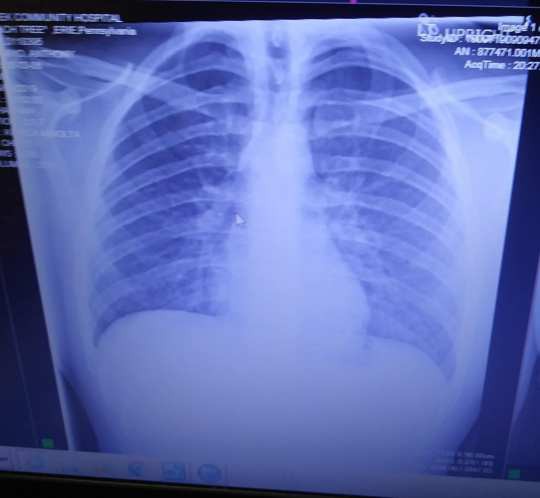

Anhthony và hình chụp X-quang hai lá phổi nghẽn đặc sau hai năm hút thuốc lá điện tử - Ảnh: KIETH MAYO

Hình chụp X-quang hai lá phổi nghẽn đặc sau hai năm hút thuốc lá điện tử của Anthony - Ảnh: KIETH MAYO

Theo báo Metro, Anthony Mayo, cậu thanh niên 19 tuổi bắt đầu đổ bệnh từ tuần trước tại Erie, bang Pennsylvania (Mỹ). Cậu không thể thở nổi do hai lá phổi tắc nghẽn vì tinh dầu từ thuốc lá điện tử đã đông đặc lại trong các túi khí trong phổi (phế nang).

Cha của Anthony, ông Kieth Mayo, cho biết bác sĩ đã cảnh báo là "Anthony mới 19 tuổi nhưng đang có lá phổi của một người 60, nghiện thuốc lá nặng đốt khoảng 2 bao mỗi ngày".

Cũng theo bác sĩ, tình trạng phổi của Anthony hiện nay rất nghiêm trọng, có thể đe dọa tính mạng.

Lúc này, các xét nghiệm cho thấy lượng ô-xy trong cơ thể anh chỉ là 36%, trong khi lượng ô-xy dưới 90% đã được cho là nguy hiểm với cơ thể.

May mắn vì được kịp thời cấp cứu, Anthony đang phục hồi sức khỏe tại Bệnh viện Cộng đồng Millcreek. Các bác sĩ đã bơm đủ 100% lượng ô-xy cho anh thở và giúp rút bỏ lượng dầu tích lại trong phổi.